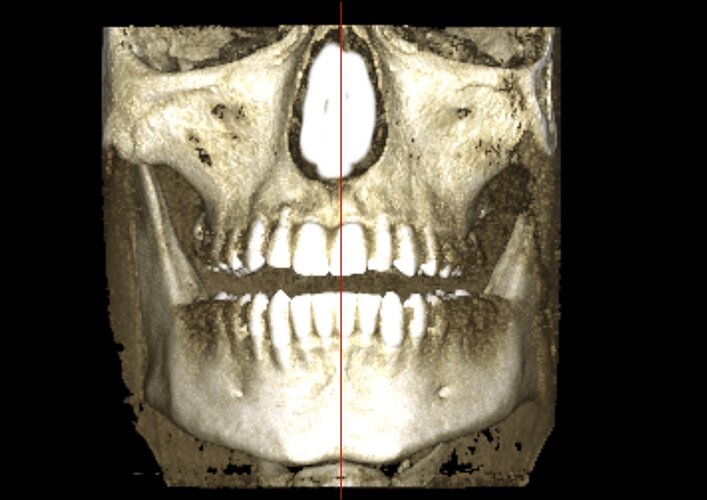

Mandibular deviation so skeletal

The chin is actually in line with the center of the skull

seems to be centered, it's just the alveolar bone playing tricks with you head, your teeth are a lil overcrowded and the "midline" in the teeth has "shifted" (thankfully because of the xray you can see that with braces a clear aligner or even a toothborne expander you could fix your overcrowded lower teeth and move the "mid-line" to the right spot, your occlusion doesn't follow the "guide lines" of the bones also I notice that the upper jaw seems to be inlign with the "midline"(teeth and the base of the nasal cavity as you can see in the image)

The alveolar bone in the upper jaw seems to be shifted